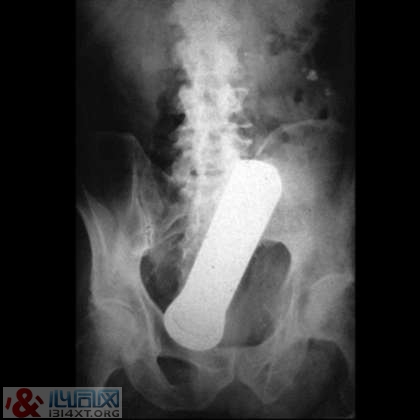

8. 手电筒